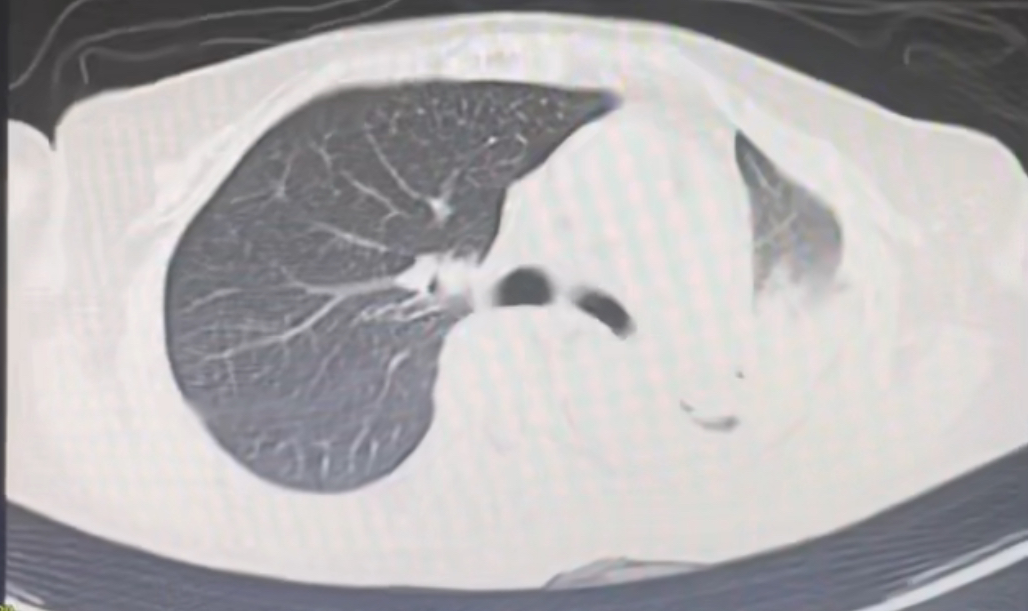

锦旗赠送人:刘女士及家人。 受表扬者:康复医学科主任衣哲、医生杨冰及其他医护人员。 近日,一面镌刻“医德高尚,仁心仁术;医术精湛,尽职尽责”的鎏金字样锦旗,被郑重送到我院康复医学科医护人员手中。这面鲜红的锦旗,承载着患者刘女士及其家属的深切感激,背后是一段跨越数月的守护历程——在医护团队协助下,曾卧床不起的刘女士逐步改善身体功能,重拾生活信心。 几个月前,一场突如其来的车祸让刘女士生命垂危。经我院ICU团队全力抢救,她的生命体征趋于稳定,但遗留颈部脊髓损伤、双下肢感觉痛觉消失等问题,需依靠气管切开套管维持呼吸、通过胃管获取营养,自主呼吸、吞咽功能丧失,生活完全无法自理。 转入康复医学科时,刘女士的状况仍面临诸多挑战。据科室衣哲主任和主管医生杨冰介绍,当时影像检查显示其肺部炎症明显、痰液淤积,日常需多次吸痰护理,部分时段需通过纤支镜清理痰液,气管切开封管与胃管拔除也需结合病情逐步推进。 针对刘女士的情况,康复医学科迅速组建由医生、康复治疗师、护士构成的协作小组。团队先对其病情进行全面评估,结合患者个体身体状况、疾病恢复阶段及家属合理期望,制定个体化、分阶段康复治疗方案,重点围绕呼吸功能改善、吞咽能力恢复、肢体活动能力提升开展工作。 康复过程中,团队先从呼吸功能干预入手:治疗师每日为刘女士进行肺部叩击、体位引流,助力气道分泌物清除;同时指导其进行缩唇呼吸训练,逐步锻炼呼吸肌力量与咳嗽能力。吞咽功能训练同步开展,治疗师采用冰刺激、空吞咽训练、门德尔松手法等方式给予指导;待其肺部炎症减轻、痰液减少后,在严密观察下尝试让她吞咽少量水与糊状食物。每一步进展,均是团队细致护理与患者积极配合的结果。 康复治疗前胸部CT提示:左肺大片状感染,左肺下叶实变,气管痰栓形成。 康复治疗后胸部CT提示:左肺感染基本吸收,原左肺实变已恢复为正常肺组织。 在呼吸、吞咽功能逐步改善的同时,肢体康复训练也有序推进。治疗师为刘女士开展关节松动术,缓解肌肉痉挛、预防关节僵硬;辅助其进行翻身训练、起立床站立训练。从需两人协助侧翻到能自主轻微移动身体,从无法坐起到顺利坐稳轮椅,过程中融入了反复的平衡训练与核心肌群强化,护士在日常护理中也会同步开展床边康复指导,鼓励刘女士主动参与,帮助其建立康复信心。 截至送锦旗当天,刘女士已在医护团队操作下成功实施气管切开套管封管、拔除胃管,能够坐在轮椅上用勺子自主进食,还能清晰向医护人员表达感谢,脸上重新展现出对生活的期待。 “这面锦旗是认可,更是我们坚守职责的动力。”康复医学科医护团队表示,科室自成立以来,始终遵循“以患者健康为中心”的服务理念,在医疗规范框架下,结合患者病情提供重症康复、功能重建、心理疏导等针对性服务,力求在专业诊疗与人文关怀上形成合力。